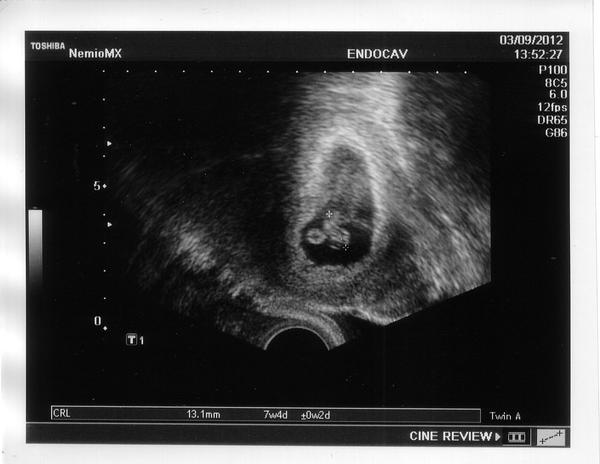

jinak tady je slíbené foto, ten den už jsem neměla sílu ho sem nahrát 😖 ....ta bublinka je žloutkový váček, který miminko vyživuje.